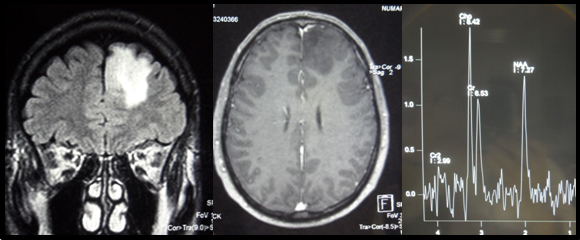

IRM cérébrale

Imagerie IRM conventionnelle :

Large lésion cérébelleuse hémisphérique postéro-supérieure gauche en hypersignal T2. Intense prise de contraste après gadolinium ; zone centrale non rehaussée liée à la présence de calcifications.

Lésion kystique adossée latéralement à la lésion apparaissant